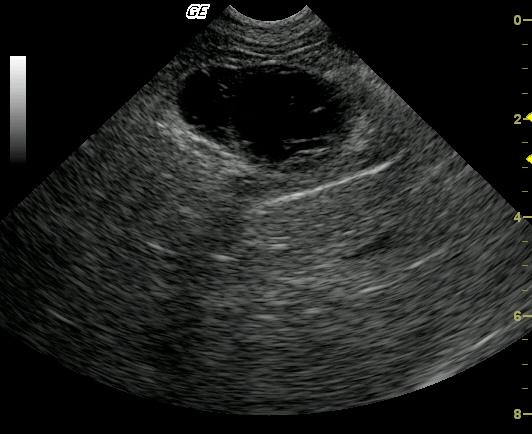

This 10 year old neutered male Beagle cross was presented for altered behavior. The physical exam was normal. CBC was normal while the blood chemistry revealed moderately elevated SAP and a slightly elevated total protein and slightly elevated globulin. The urinalysis revealed USG of 1.021 and 4+ proteinuria with inactive sediment. ACTH stimulation test was normal.